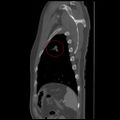

3. SPECT(Single-photon emission computed tomography) 촬영

1. 사진-1

2. 오른쪽 폐는 3개(RUL RML RLL)로 나누어져 있고, 왼쪽 폐는 2개(LUL, LLL)로 나누어져 있다.

1. 내 경우 폐기능은 (암이 있는) 왼쪽 45%, 오른쪽 55% 를 보이고 있다. 정상인인 경우 왼쪽 오른쪽 비율이 궁금하다.

2. 문제의 왼쪽 폐 위쪽(LUL)은 체적 30%, 기능 24%를 차지하고 있다. 기능이 체적이 비례하지 않고 있다. 원인이 암 때문인지 궁금하다.